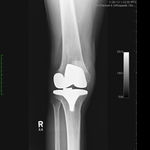

Patient seen with Bilateral Knee Pain and had been unable to walk for two (2) years.

On clinical and radiological examination, he was assessed as having Severe Primary Osteoarthritis of both knees.

Bilateral Total Knee Replacement was recommended, and performed on July 27th 2011. Since surgery, the patient has made good progress and can now mobilize with the aid of a walker.

His x-rays and clinical examination suggest good early outcome with a fully mobilized patient with pain free knees and the ability to walk independently.